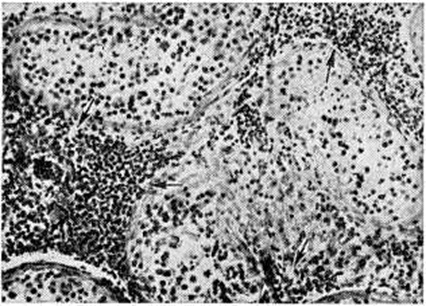

Рис. 2.

Микропрепарат миокарда при интерстициальном сыпнотифозном миокардите: инфильтрация стромы миокарда преимущественно плазматическими клетками (указаны стрелками); окраска гематоксилин-эозином; ×400.

Характерным признаком Сыпной тиф эпидемический является также и интерстициальный миокардит (смотри полный свод знаний), проявляющийся очаговой, реже диффузной инфильтрацией стромы миокарда плазматическими клетками в сочетании с большим или меньшим образованием сыпнотифозных узелков и слабыми изменениями кардиомиоцитов (рисунок 2).